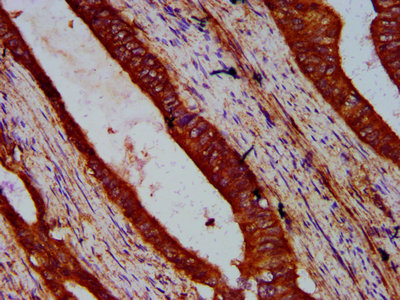

IHC image of CSB-PA823478LA01HU diluted at 1:500 and staining in paraffin-embedded human colon cancer performed on a Leica BondTM system. After dewaxing and hydration, antigen retrieval was mediated by high pressure in a citrate buffer (pH 6.0). Section was blocked with 10% normal goat serum 30min at RT. Then primary antibody (1% BSA) was incubated at 4°C overnight. The primary is detected by a biotinylated secondary antibody and visualized using an HRP conjugated SP system.